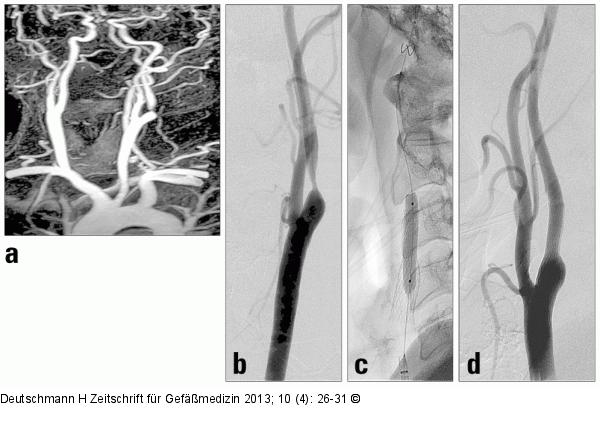

Abbildung 1a-d: Karotisstenose 55-jähriger Patient mit hochgradiger asymptomatischer Abgangsstenose der A. carotis interna links. (a): Kontrastgestützte MR-Angiographie der zervikalen und intrakraniellen Arterien. Darstellung der hochgradigen Abgangsstenose der A. carotis interna links. Variantenhafter Abgang der A. carotis communis links aus dem Truncus brachiocephalicus (sog. boviner Abgangsmodus). (b): Die digitale Subtraktionsangiographie (DSA) bestätigt die 85-%-Stenose. (c): Nach Platzierung eines distalen Protektionsfilters Vordilatation mit einem 2,5/20-mm-Ballon, Einbringen eines selbstexpandierenden Nitinolstents (8–10/40 mm) und Nachdilatation mit einem 5/30-mm-Ballon. (d): Die Abschlussangiographie zeigt eine gute Entfaltung des Stents ohne Hinweis auf Residualstenose. |

55-jähriger Patient mit hochgradiger asymptomatischer Abgangsstenose der A. carotis interna links. (a): Kontrastgestützte MR-Angiographie der zervikalen und intrakraniellen Arterien. Darstellung der hochgradigen Abgangsstenose der A. carotis interna links. Variantenhafter Abgang der A. carotis communis links aus dem Truncus brachiocephalicus (sog. boviner Abgangsmodus). (b): Die digitale Subtraktionsangiographie (DSA) bestätigt die 85-%-Stenose. (c): Nach Platzierung eines distalen Protektionsfilters Vordilatation mit einem 2,5/20-mm-Ballon, Einbringen eines selbstexpandierenden Nitinolstents (8–10/40 mm) und Nachdilatation mit einem 5/30-mm-Ballon. (d): Die Abschlussangiographie zeigt eine gute Entfaltung des Stents ohne Hinweis auf Residualstenose. |